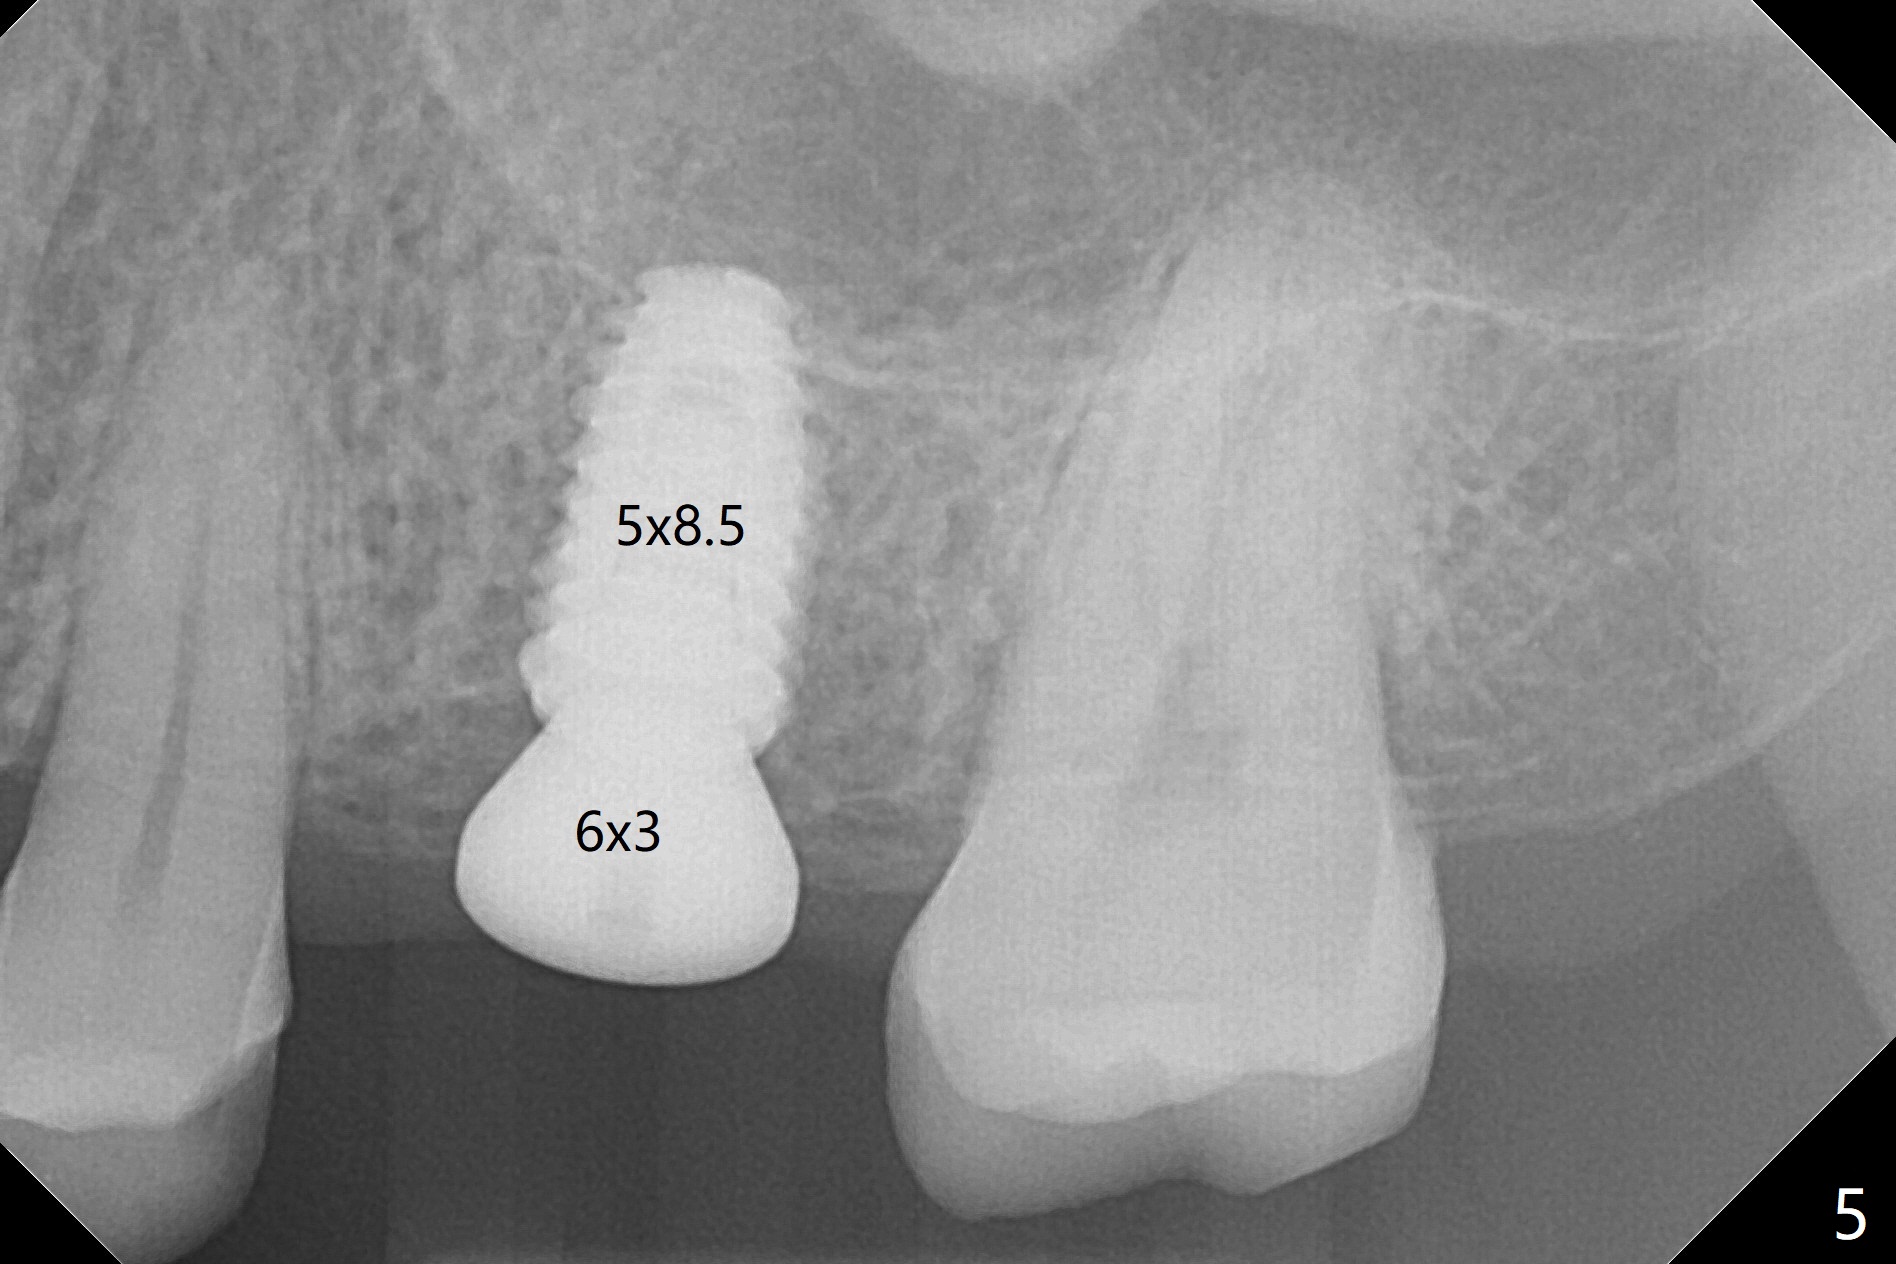

The guide is removed when the osteotomy at #14 (Fig.1 (8.45 mm bone height)) is finished in an under drilling manner in depth (Fig.2). The middle of the apical remaining bone is so thin (Fig.3 (white line representing the sinus floor)) that it can be pushed up like ping pong or eggshell (Fig.4 arrow). A 5x8.5 mm implant is placed with satisfactory insertion torque and depth, followed by insertion of a 6x3 mm healing abutment (Fig.5). There is mild resorption of the sinus floor distally 3.5 months postop, although the implant remains stable (Fig.6).